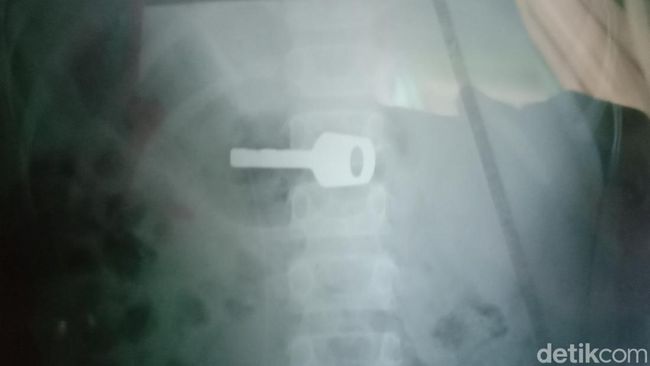

Zul (9) dan penampakan kunci yang tak sengaja ia telan di Indramayu (Foto: Ony Syahroni/detikJabar)

Kunci gembok, saat ini masih bersarang di tubuh Zul (9), warga Kelurahan Lemahabang, Kabupaten Indramayu, Senin (19/9/2022). Kunci itu masuk tanpa sengaja saat Zul menunggu kepulangan kakaknya yang sedang bekerja.

Tidak lama, sekitar pukul 23.00 WIB, Zul merintih sakit kepada ibunya karena kunci gembok cadangan yang dipegangnya masuk ke dalam tubuh.

Zul (9) dan penampakan kunci yang tak sengaja ia telan di Indramayu Foto: Sudedi Rasmadi/detikJabar

"Di rumah sakit, Zul hanya diinfus dan rontgen. Kita habis sekitar Rp1,8 juta untuk biaya tersebut," kata Nina menceritakan nasib Anaknya.